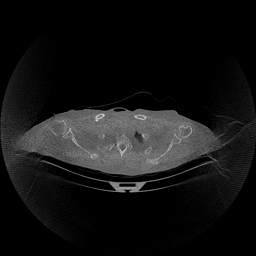

The results for simulated noisy data are shown in Fig. 2. The first and third rows display two representative slices from the test set, and the second and fourth rows present the corresponding error maps. The traditional WCE method suppresses cupping artifacts and recovers some missing anatomical structures but still shows noticeable deviations from the ground truth. Predictions from the four diffusion-based models demonstrate a markedly improved ability to restore anatomical structures. Among them, cDDPM fails to fully reconstruct the patient bed and retains residual noise in its outputs. This noise is attributable to an incomplete reverse denoising process rather than residual Poisson noise, as evidenced in our noise-free experiments (Fig. 5 in the Appendix). PatchDiffusion, diffusionGAN, and I2SB achieve similar visual quality, with I2SB producing the cleanest and most consistent reconstructions.

The experimental results on clinical head data are shown in Fig. 4. The reference images were reconstructed using the fast iterative shrinkage-thresholding algorithm (FISTA) with total variation regularization from non-truncated projection data. In the WCE reconstructions (Fig. 4(b)), severe truncation prevents accurate recovery of anatomical structures outside the FOV. Despite being trained solely on simulated data with a domain gap, all deep learning models can restore a substantial portion of the missing anatomy. Among them, the diffusion-based methods recover soft-tissue boundaries more faithfully than the conventional deep learning approach FBPConvNet, highlighting their stronger image generation capability. However, cDDPM reconstructions exhibit more noticeable noise than those from other methods, consistent with the simulated data results. The patchDiffusion model introduces artifacts within the FOV, likely due to its patch-wise processing strategy. While I2SB shares the same limitations as other diffusion models in perfectly restoring soft-tissue detail, it produces fewer residual noise patterns and fewer artifacts within the FOV boundaries. Overall, Fig. 4 demonstrates the strong efficacy of I2SB in reconstructing real CBCT data.